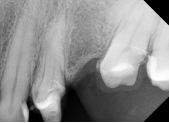

Descripción del Caso: Advanced Cases en Calcified Canal Cases

Este caso clínico se clasifica como Advanced Cases debido a su anatomía compleja: conductos con atresias y doble curvatura en bayoneta, particularmente en el conducto vestibular.

Tales configuraciones anatómicas no solo dificultan la permeabilización inicial del conducto, sino que también elevan el riesgo de transporte apical, formación de escalones y fractura instrumental durante la instrumentación.